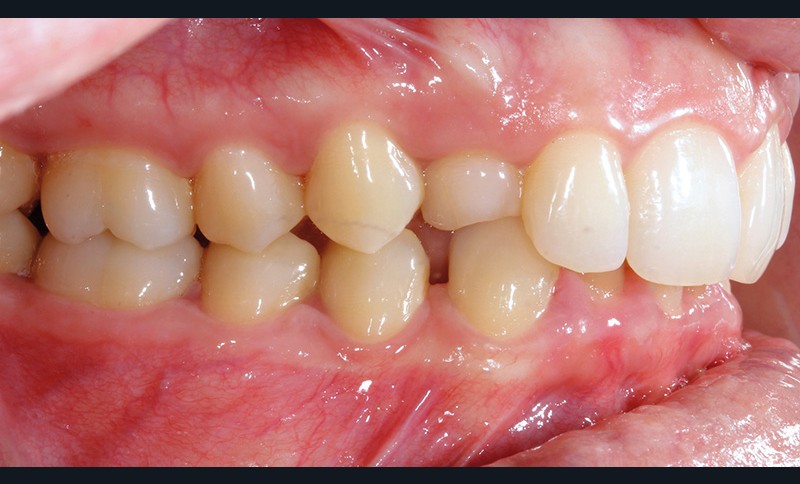

Aline se présente à la consultation pour une demande esthétique concernant ses deux canines lactéales qu’elle trouve trop petites et trop blanches (fig. 1a). Elle présente une classe II squelettique légère sur un schéma méso-divergent. D’un point de vue dentaire, une supraclusion est associée à une classe II d’Angle complète à gauche et de 4 mm à droite. Les canines maxillaires sont incluses (une vestibulaire et une palatine), avec persistance de leurs dents lactéales sur l’arcade (fig. 1b-h).